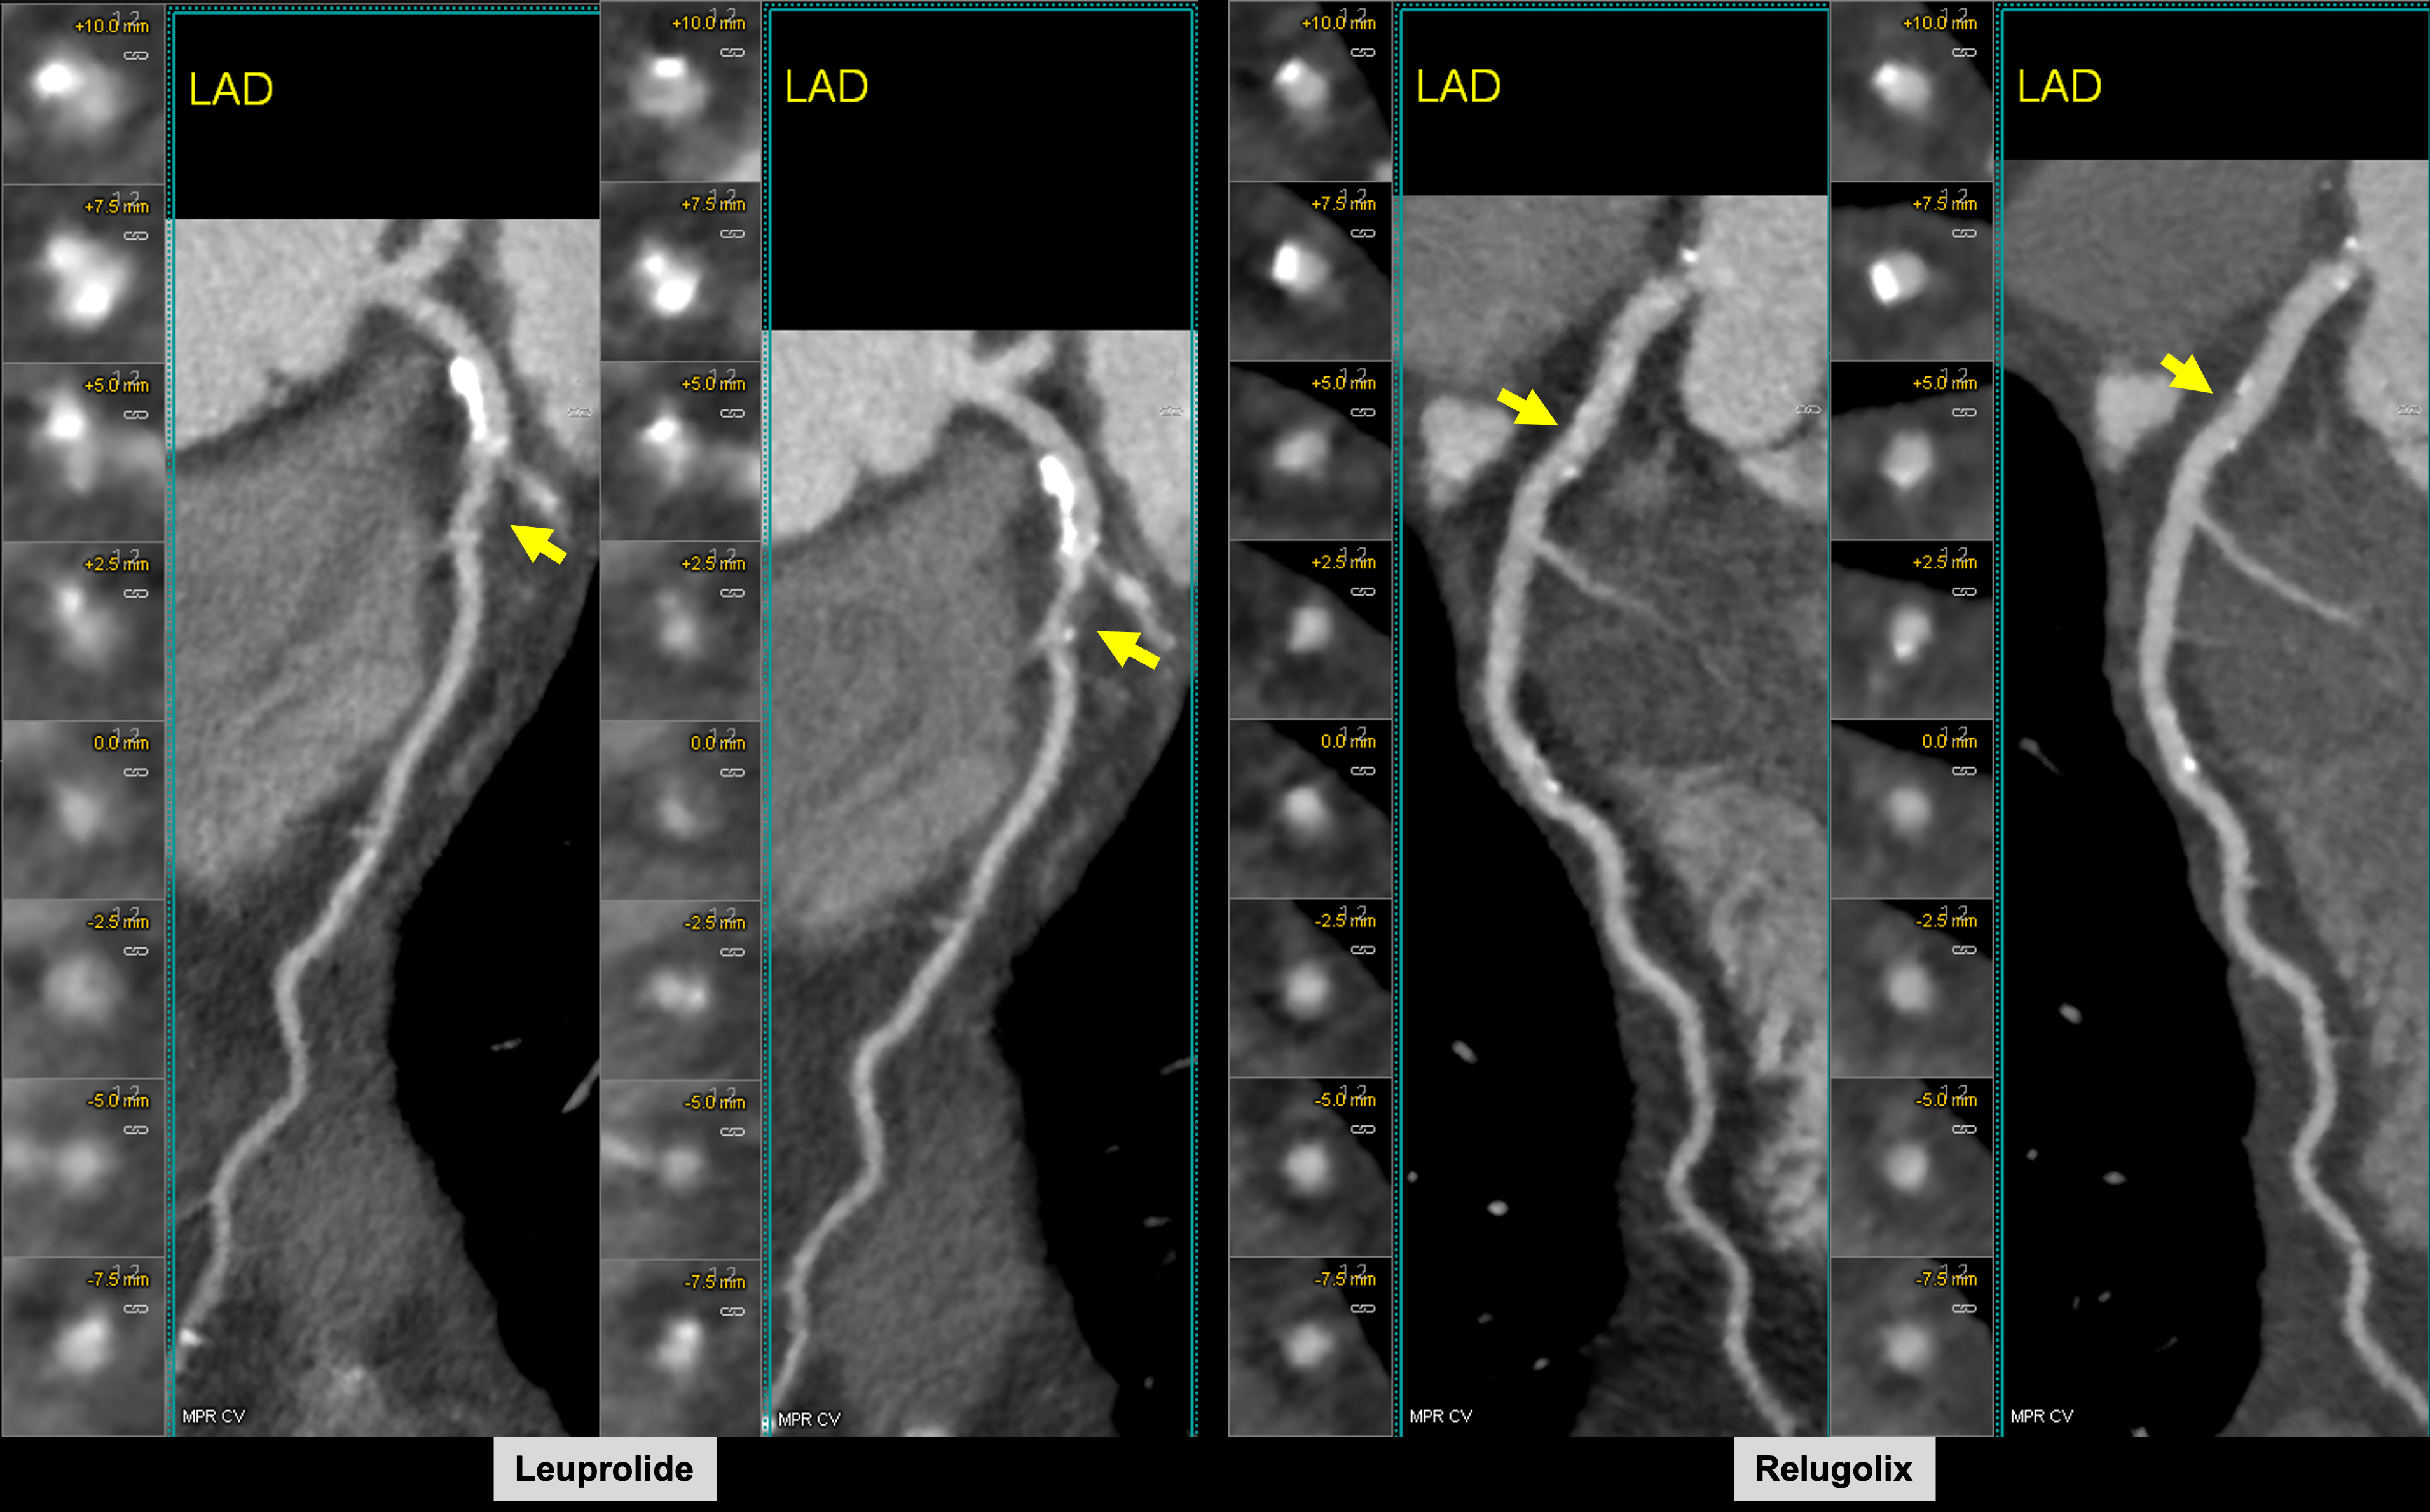

Accelerated Coronary Atherosclerosis Following Relugolix Versus Leuprolide Androgen Deprivation Therapy in Men with Prostate Cancer (REVELUTION): An Open-Label Randomized Controlled Trial

Abstract Body (Do not enter title and authors here): Purpose: Androgen deprivation therapy (ADT) for prostate cancer (PCa) is associated with cardiovascular (CV) morbidity, yet the biological basis remains unclear. Recent studies have yielded conflicting results regarding the CV safety of gonadotropin releasing hormone (GnRH) agonists versus antagonists. Relugolix Versus Leuprolide Cardiac Trial (REVELUTION, NCT05320406) was designed to test the hypothesis that ADT-associated CV risk is mediated by accelerated coronary atherosclerosis and is more prominent with the GnRH-agonist leuprolide compared with the GnRH-antagonist relugolix.

Results: Of the 94 men enrolled from 06/2022 to 03/2024, 90 (28 RT alone, 31 RT plus leuprolide, and 31 RT plus relugolix) completed study for analysis. Median change in TPV was higher (P=.02) with leuprolide (+52.0 [19.5-159.0] mm3) compared with relugolix (+25.0 [-6.0-46.0] mm3) and no ADT (+13.0 [-19.0-45.0] mm3). Compared with no ADT, leuprolide was associated with a significantly greater increase in TPV (estimated difference +79.1 mm3, P=.004), NCPV (+71.9 mm3, P=.001), CPV (CPV +19.9 mm3, P=.04), and LAPV (+5.1 mm3, P=.03) after adjusting for baseline plaque volume, age, and statin use. Compared with no ADT, relugolix did not result in a significant change in TPV (estimated difference +10.5 mm3, P=.69), NCPV (+7.2 mm3, P=.73), CPV (+8.9 mm3, P=.34), or LAPV (+1.3 mm3, P=.56). With a median follow-up of 23.3 (IQR 18.2-29.1) months, 3 patients (9.7%) in the leuprolide arm, 0 patients in the relugolix arm, and 1 patient (3.6%) in the no ADT arm experienced a MACE.

Conclusion: ADT for PCa is associated with accelerated coronary atherosclerosis within 12 months and is significantly higher with GnRH-agonist leuprolide compared with GnRH-antagonist relugolix.